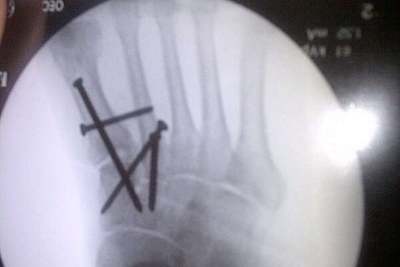

Kenan Sofuoglu wird beim morgigen Indianapolis-GP fehlen. Der Türke brach sich im zweiten freien Training am Freitag nach einem Highsider mehrere Mittelfussknochen rechts.

Weil sich die Knochen übereinandergeschoben haben, wurde der Technomag-CIP-Pilot noch am selben Tag im Krankenhaus von Indianapolis operiert. Insgesamt vier Nägel mussten eingesetzt werden, um alle Knochen zu fixieren. Sofuoglu kämpft nun darum, nächstes Wochenende in Misano wieder dabei zu sein.